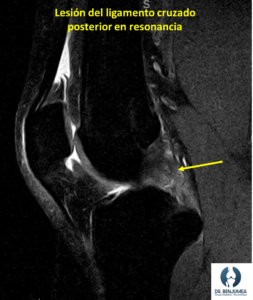

Generalmente los pacientes contáis como ha sido el golpe, y lo que sentís a partir de ese momento, lo que puede hacer sospechar la lesión, además existen unas maniobras que realizamos en consulta que nos ayudan a diagnosticar la lesión. Ante la sospecha clínica una resonancia nos confirmara el diagnóstico y si existen lesiones acompañantes.